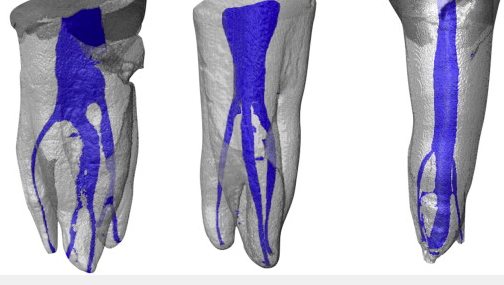

Conventional intra-oral radiography provides clinicians with cost-effective, high-resolution imaging that continues to be the front-line method for dental imaging. However, it is clear that there are many specific situations where the 3-D images produced by CBCT facilitates diagnosis and influences treatment. The usefulness of the CBCT cannot be disputed. It is a valuable task-specific imaging modality, producing minimal radiation exposure to the patient and providing maximal information to the clinician.